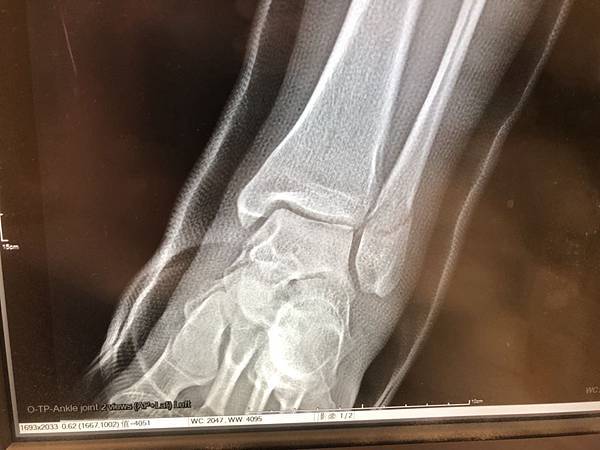

因為左邊這張X光片跟右邊的受傷第一天拍的X光片比起來感覺一點變化都沒有啊!!!

去了之後我讓我固定看診的院長,吳郡芳醫師看X光照片,